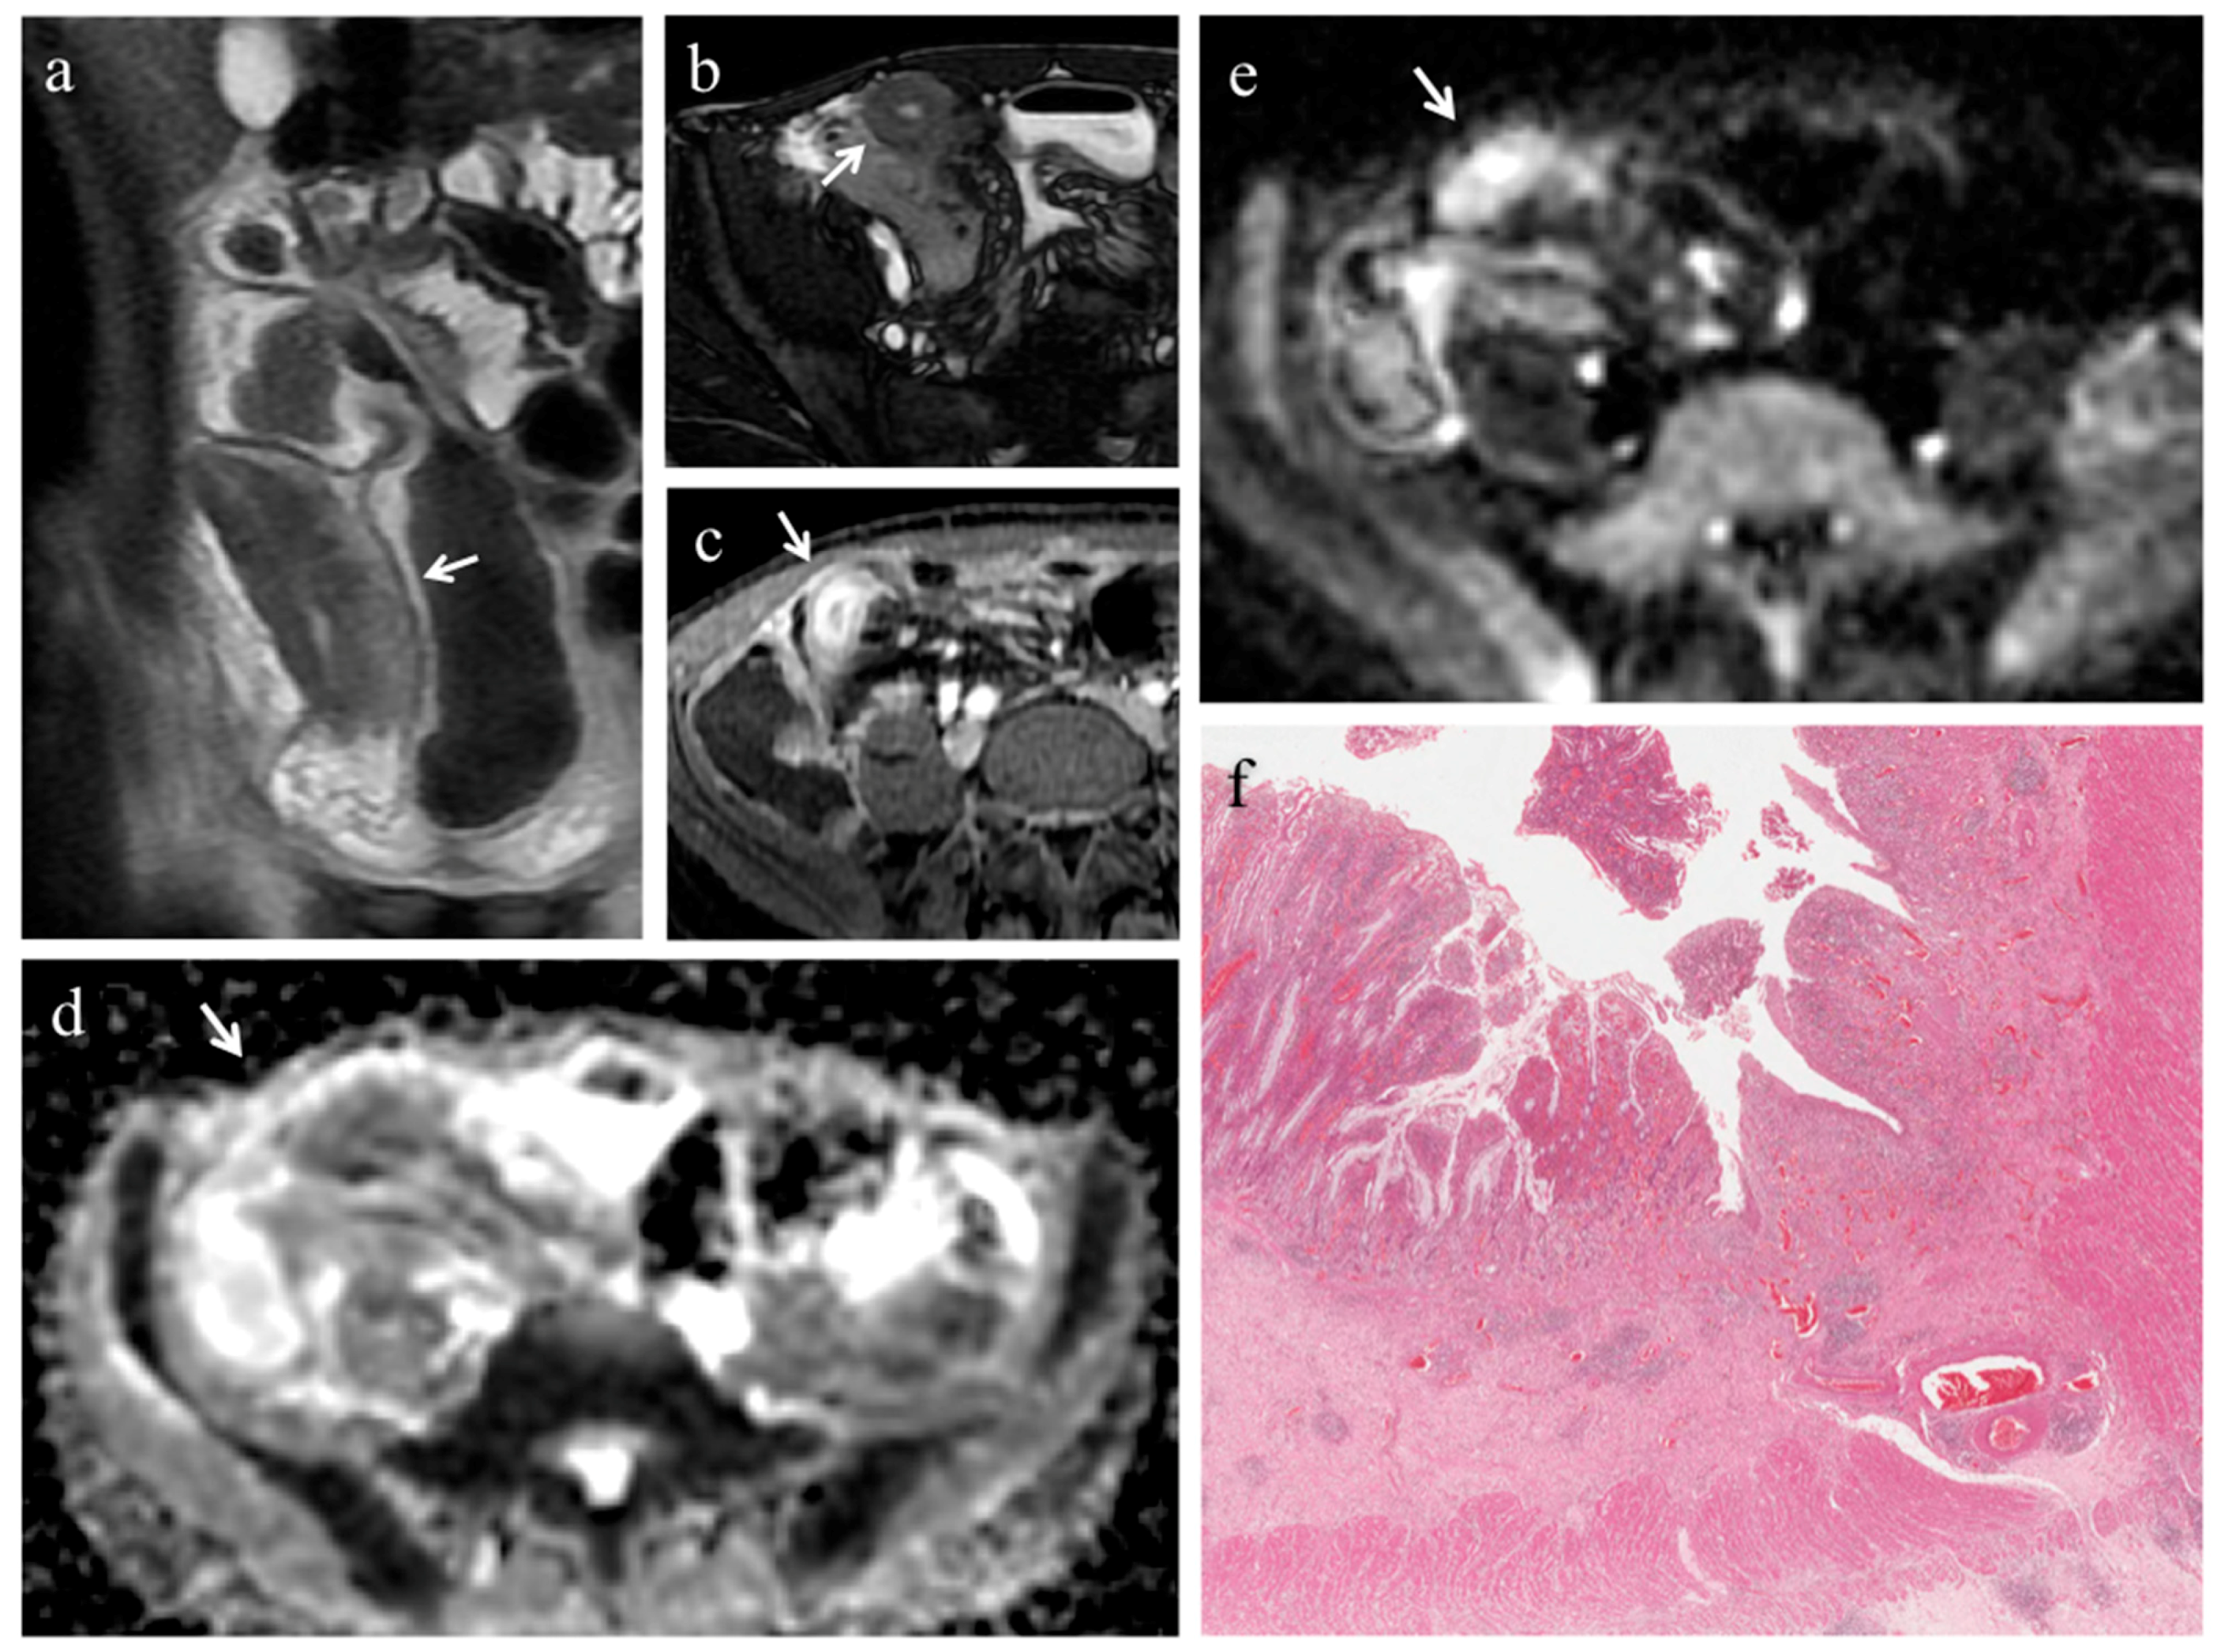

3.3. Analysis of Conventional MRE Sequences

3.4. Analysis of DWI Quantitative Measures (ADC)